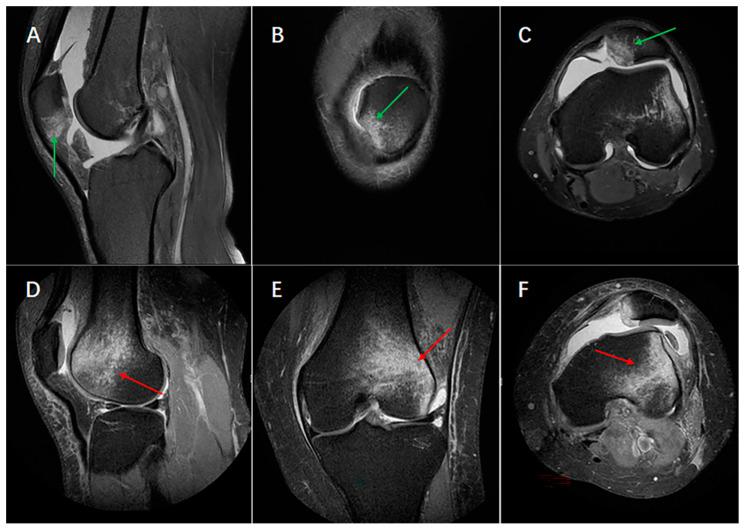

Different bone bruise patterns observed using magnetic resonance imaging (MRI) after non-contact anterior cruciate ligament (ACL) rupture and lateral patellar dislocation may indicate different knee injury mechanisms. In this study, 77 ACL ruptures and 77 patellar dislocations in knee MR images taken from patients with bone bruises at our institution between August 2020 and March 2022 were selected and analyzed. In order to determine typical bone bruising patterns following by ACL rupture and patellar dislocation, sagittal- and transverse-plane images were used to determine bone bruise locations in the directions of medial-lateral and superior-inferior with MR images. The presence, intensity, and location of the bone bruises in specific areas of the femur and tibial after ACL rupture and patellar dislocation were recorded. Relative bone bruise patterns after ACL rupture and patellar dislocation were classified. The results showed that there were four kinds of bone bruise patterns (1-, 2-, 3-, and 4- bone bruises) after ACL rupture. The most common two patterns after ACL rupture were 3- bone bruises (including the lateral femoral condyle and both the lateral-medial tibial plateau, LF + BT; both the lateral-medial femoral condyle and the lateral tibial plateau, BF + LT; and the medial femoral condyle and both the medial and lateral tibial plateau, MF + BT) followed by 4- bone bruises (both the lateral-medial femoral condyle and the tibial plateau, BF + BT), 2- bone bruises (the lateral femoral condyle and tibial plateau, LF + LT; the medial femoral condyle and the lateral tibial plateau, MF + LT; the lateral femoral condyle and the medial tibial plateau, LF + MT; the medial femoral condyle and the tibial plateau, MF + MT; both the lateral-medial tibial plateau, 0 + BT), and 1- bone bruise (only the lateral tibial plateau, 0 + LT). There was only a 1- bone bruise (the latera femoral condyle and medial patella bone bruise) for patellar dislocation, and the most common pattern of patellar dislocation was in the inferior medial patella and the lateral anterior inferior femur. The results suggested that bone bruise patterns after ACL rupture and patellar dislocation are completely different. There were four kinds of bone bruise patterns after non-contact ACL rupture, while there was only one kind of bone bruise pattern after patellar dislocation in patients, which was in the inferior medial patella and lateral anterior inferior femur.

使用磁共振成像(MRI)观察到的非接触性前交叉韧带(ACL)断裂和髌骨外侧脱位后的不同骨挫伤模式可能表明不同的膝关节损伤机制。在本研究中,选取并分析了2020年8月至2022年3月期间在我院拍摄的有骨挫伤的膝关节MR图像中的77例ACL断裂和77例髌骨脱位。为了确定ACL断裂和髌骨脱位后的典型骨挫伤模式,利用矢状面和横断面图像,通过MR图像确定股骨和胫骨内外侧及上下方向的骨挫伤位置。记录ACL断裂和髌骨脱位后股骨和胫骨特定区域骨挫伤的存在、强度和位置。对ACL断裂和髌骨脱位后的相关骨挫伤模式进行分类。结果显示,ACL断裂后有四种骨挫伤模式(1级、2级、3级和4级骨挫伤)。ACL断裂后最常见的两种模式是3级骨挫伤(包括外侧股骨髁和胫骨内外侧平台,LF + BT;股骨内外侧髁和外侧胫骨平台,BF + LT;内侧股骨髁和胫骨内外侧平台,MF + BT),其次是4级骨挫伤(股骨内外侧髁和胫骨平台,BF + BT)、2级骨挫伤(外侧股骨髁和胫骨平台,LF + LT;内侧股骨髁和外侧胫骨平台,MF + LT;外侧股骨髁和内侧胫骨平台,LF + MT;内侧股骨髁和胫骨平台,MF + MT;胫骨内外侧平台,0 + BT)和1级骨挫伤(仅外侧胫骨平台,0 + LT)。髌骨脱位只有1级骨挫伤(外侧股骨髁和内侧髌骨骨挫伤),最常见的髌骨脱位模式位于髌骨内下和股骨外侧前下。结果表明,ACL断裂和髌骨脱位后的骨挫伤模式完全不同。非接触性ACL断裂后有四种骨挫伤模式,而患者髌骨脱位后只有一种骨挫伤模式,位于髌骨内下和股骨外侧前下。